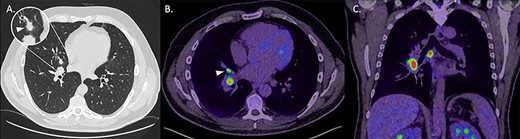

(A) Axial non-contrast CT thorax on lung windows demonstrating a 13-mm, spiculated perihilar lesion within the middle lobe of the right lung (magnified). (B) Axial fused image from a PET-CT demonstrating elevated uptake within the middle lobe lesion (arrowhead) as well as within enlarged ipsilateral hilar lymph nodes. (C) Coronal fused image from a PET-CT demonstrating increased uptake in abnormal right hilar and subcarinal lymph nodes.

CT thorax showed a 1.3 cm spiculated right middle lobe nodule, concerning for a primary lesion. Subsequent PET-CT showed intense uptake there and in the right hilum and a sub-carinal lymph node (Fig. 3). An endobronchial ultrasound bronchoscopy showed adenocarcinoma in station 11R and 7. Diagnoses of T2N1M0 left tonsil SCC (TNM 8 classification) and T2N2 (single station) M0 adenocarcinoma were made.